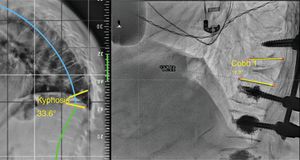

In the local deformity group (stage 1), this can be flexible (1A), if a reduction in angulation greater than 50% is observed in the decubitus position with respect to the X-ray (Fig. 2) in standing position, or rigid (1B), when no reduction is seen in the decubitus position (Fig. 3).13 Finally, this local deformity may be compensated (C) when the standing teleradiography shows the SVA to be within normal parameters, or non-compensated (NC), when the teleradiography shows an out-of-range SVA. It should be remembered that SVA varies with age, and we are not looking for as rigorous a correction in the elderly patient as in the young patient.8